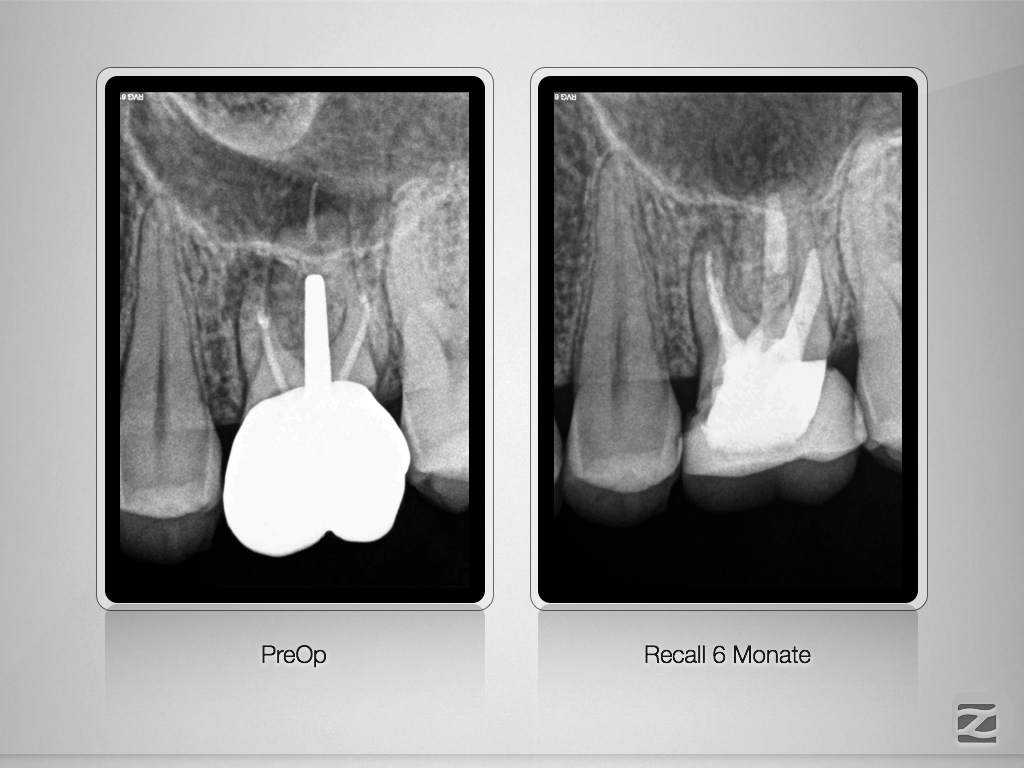

26D.004

Revision nach Resektion